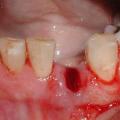

Фото 1. Простое удаление. Зачастую в данном случае удаляется шатающийся зуб, доступно расположенный для стоматолога.

Простое

Два наиболее распространенных способа экстракции коренных зубов: простой и хирургический. Первый используется для удаления видимых зубов. Это наименее травматичный вариант, когда зуб захватывается щипцами, немного расшатывается и извлекается.